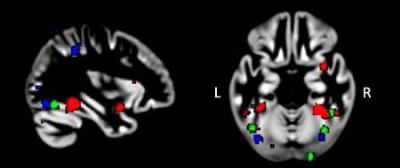

Distribuzione delle aree del cervello piu’ attive negli autistici secondo il campo di trattamento: ” Visi” in rosso, “Oggetti” in verde e “Parole” in blu. Foto: Human Brain Mapping, Wiley-Blackwell, Inc.